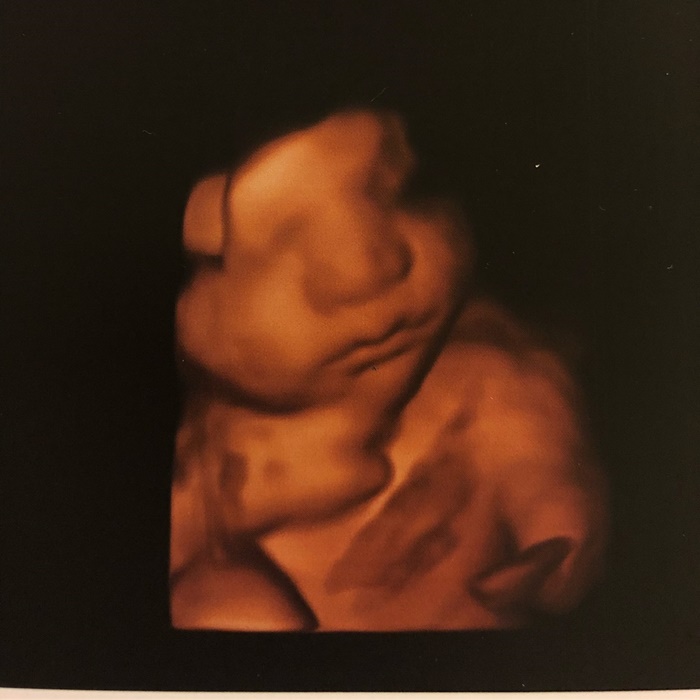

โดยล่าสุด (3 มีนาคม 2561) ชาคริต ก็ได้เผยภาพอัลตราซาวด์ของ น้องโพธิ์ แบบ 4D เห็นโครงหน้าชัดแจ๋ว พร้อมข้อความว่า "First Glimpse of Bodhi’s 4D ultrasound... see u in 2 months baby boy" ซึ่งในภาพ น้องโพธิ์ ก็มีรอยยิ้มละมุนส่งมาให้ด้วย น่ารักน่าเอ็นดูสุด ๆ เลยล่ะ

ขนาดภาพอัลตราซาวด์ยังน่าเอ็นดูขนาดนี้ ถ้าคลอดมาแล้วเชื่อว่า น้องโพธิ์ จะต้องกลายเป็นขวัญใจของคนรักเด็กอย่างแน่นอนเลยค่ะ